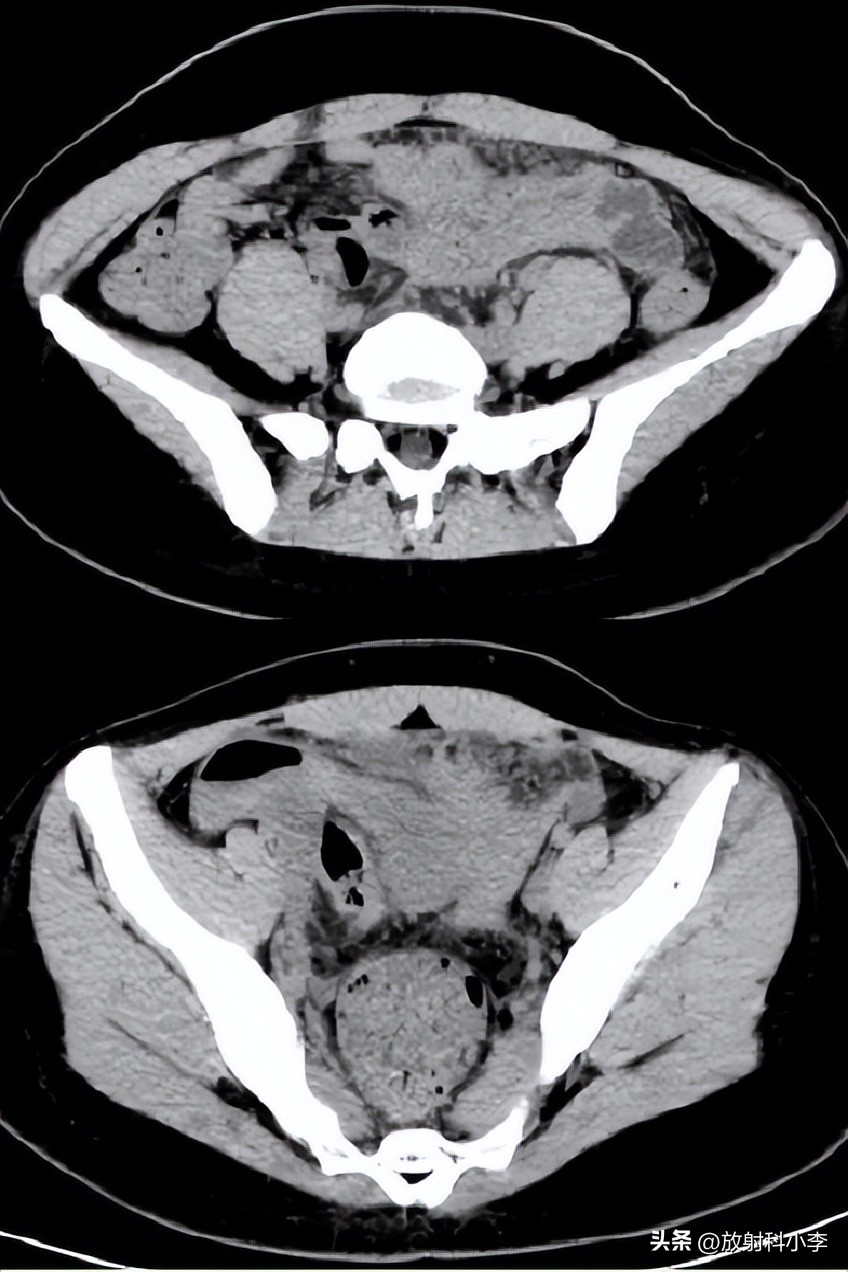

case 2. F,27Y,下腹痛2天,加剧5小时

妇科检查:宫颈举痛、摇摆痛;后穹窿穿刺4ml不凝血;

术前CT示:腹腔内出血,左侧附件区囊性灶,伴周围盆腔环状稍高密度影,???考虑异位妊娠可能?

术中:子宫前位,正常大小,左侧输卵管壶腹部破裂出血,清理出血块2000ml,积血块中见绒毛组织。

术后诊断:左侧卵巢妊娠破裂。